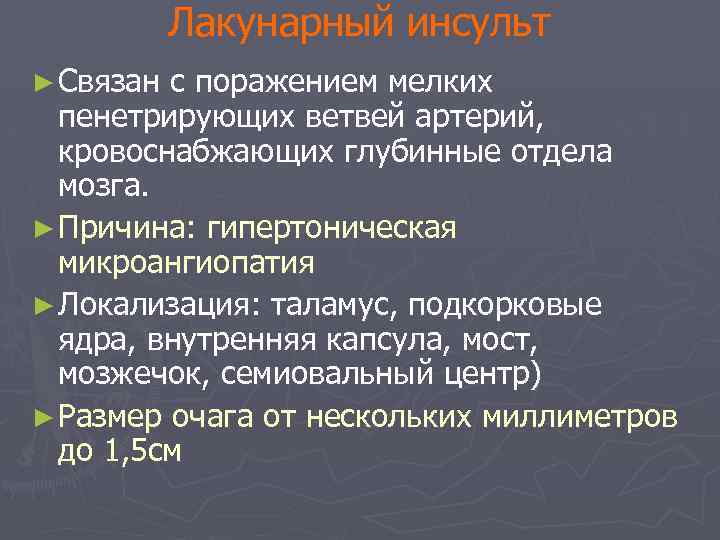

Лакунарный инсульт ► Связан с поражением мелких пенетрирующих ветвей артерий, кровоснабжающих глубинные отдела мозга. ► Причина: гипертоническая микроангиопатия ► Локализация: таламус, подкорковые ядра, внутренняя капсула, мост, мозжечок, семиовальный центр) ► Размер очага от нескольких миллиметров до 1, 5 см